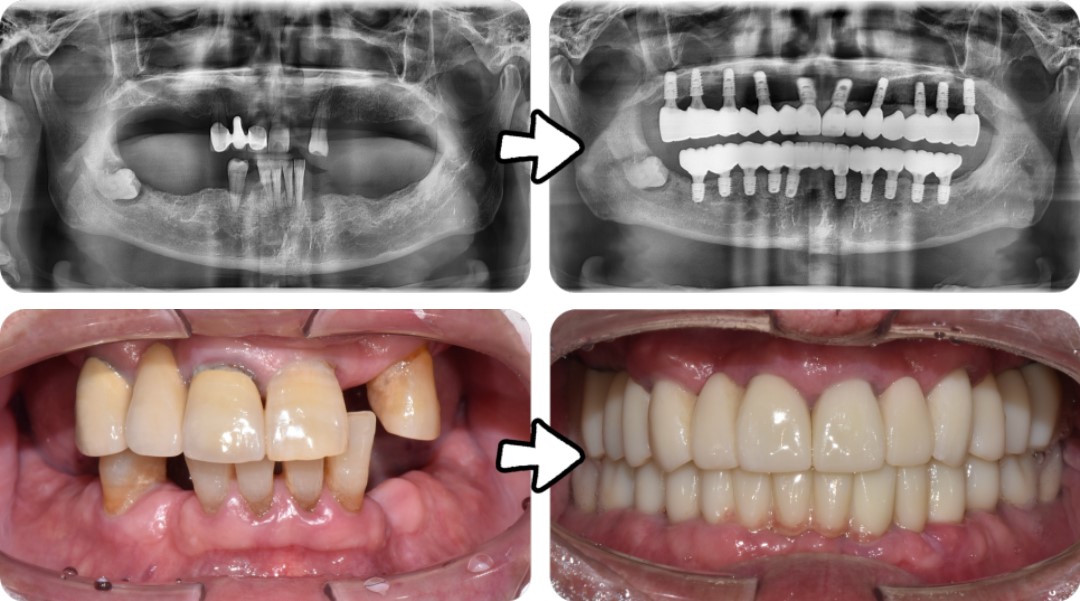

2023년 7월 내원 당시 구강 상태

파노라마 사진에서 보이다시피 위, 아래 어금니는 오래전에 상실한 상태였고

남아있는 앞니마저 흔들리고 잇몸뼈도 많이 녹아,

앞으로 1년도 채 안돼서 빠질 가능성이 높아 보였습니다.

김태수님은 위 10개, 아래 10개의 임플란트를 식립하고

뼈이식을 동반한 전체 임플란트 치료를 받으셨는데요.

이전부터 앓고 계시던 만성 치주염으로 이미 잇몸뼈가 많이 소실된 상태인데다가,

틀니를 5년 정도 사용하셔서 잇몸뼈의 폭과 높이가

임플란트를 심기에 뼈가 많이 부족한 상태였습니다.